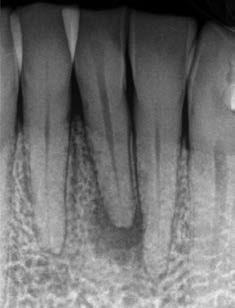

1. a–g. ábrák: A direkt pulpasapkázás lépései. Kiindulási bitewing-felvétel: A meglévő restaurátum közel helyezkedett el a pulpakamrához (a). Kiindulási periapicalis felvétel: Nincs periapicalis elváltozás fennállására utaló jel (b). A pulpaexpozíció (c). A vérzéscsillapítás céljából 20 másodpercen keresztül steril vattagombóccal történő kompressziót követően látható pulpaseb (d). A pulpasapkázás céljából behelyezett anyag, a széli részek tisztázása előtt készült felvétel (e). A röntgenárnyékot nem adó ideiglenes tömés behelyezése után készült felvétel (f). Az első ülés végén a röntgenárnyékot nem adó ideiglenes töméssel ellátott fogról készített röntgenfelvétel (g).

2. ábra: A hat hónapos kontroll alkalmával készített röntgenfelvételen vastag dentinhíd látható a pulpasapkázó anyag alatt.

3. ábra: A hároméves kontroll alkalmával készített röntgenfelvételen megfigyelhető a restaurátum pontos illeszkedése.

A kezelést követően a beteg tünetmentes volt. A kérdéses fog a kontrollvizsgálatok során végzett szenzibilitástesztekre fiziológiás reakciókat adott. A hat hónapos kontroll alkalmával készített röntgenfelvételen a sérülésnek megfelelően széles dentinhidat észleltünk (2. ábra). A restaurátum a hároméves kontroll során is megfelelőnek bizonyult (3. ábra)